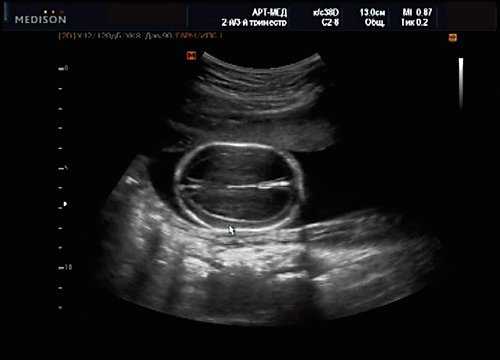

Антенатально при равных величинах давления в желудочках сердца и в предсердиях объемной перегрузки не возникает. В связи с этим ни один из эхокардиографических гемодинамических признаков, используемых у детей и взрослых, не выявляется у плода. К эхокардиографическим проявлениям порока антенатально относится только прямой признак - перерыв ультразвукового луча в области дефекта. Размеры сердца, соотношение размеров желудочков сердца не отличаются от нормы (рис. 5).

Рис. 5. Четырехкамерное сечение сердца плода. Стрелкой указан первичный дефект межпредсердной перегородки (АVS).